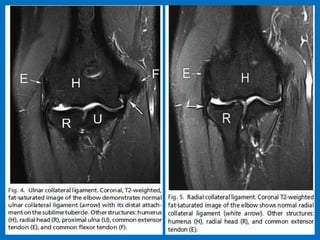

UCL (black arrows) and overlying common flexor tendon (black arrowhead) on the medial side (MED).

On the lateral side (LAT ) is the radial collateral ligament with an adjacent synovial fold (white arrow),

the annular ligament (white arrowhead ), and the overlying extensor carpi radialis brevis origin (open

arrow). (b) Coronal T2-weighted FS MR image through the elbow demonstrates the posterior band of

the UCL (black arrow) on the medial side and LUCL (white arrows) on the lateral side.